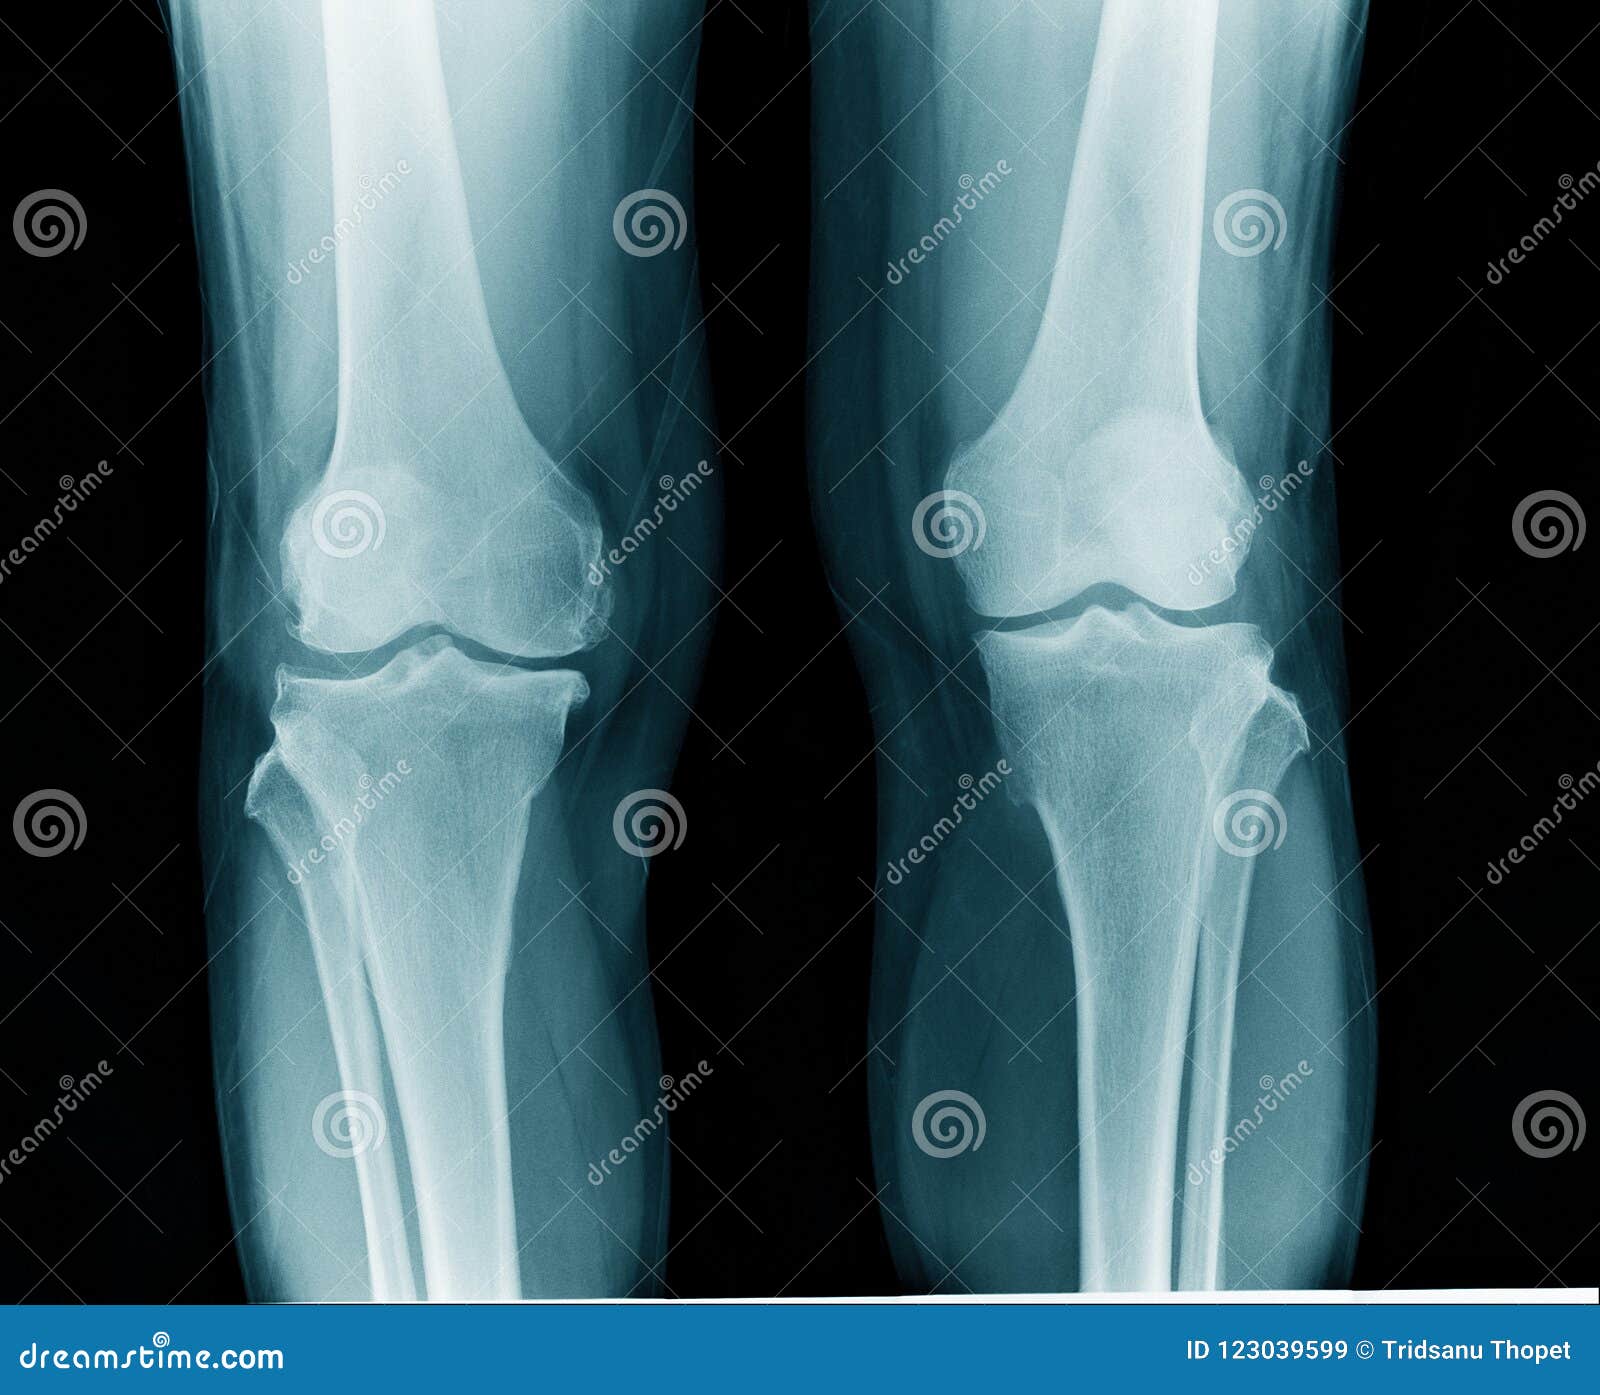

From mappingmemories.ca

columpio ángulo Tranquilidad de espíritu artritis reumatoide rodilla Que Causa La Artritis En Las Rodillas la enfermedad suele afectar las manos, las rodillas y los tobillos, y generalmente la misma articulación en ambos lados del. Una rodilla sana puede flexionarse y. a medida que avanza la enfermedad, los síntomas suelen extenderse a las muñecas, las rodillas, los tobillos,. ¿cuáles son las causas de la artritis de rodilla? la osteoartritis es la. Que Causa La Artritis En Las Rodillas.